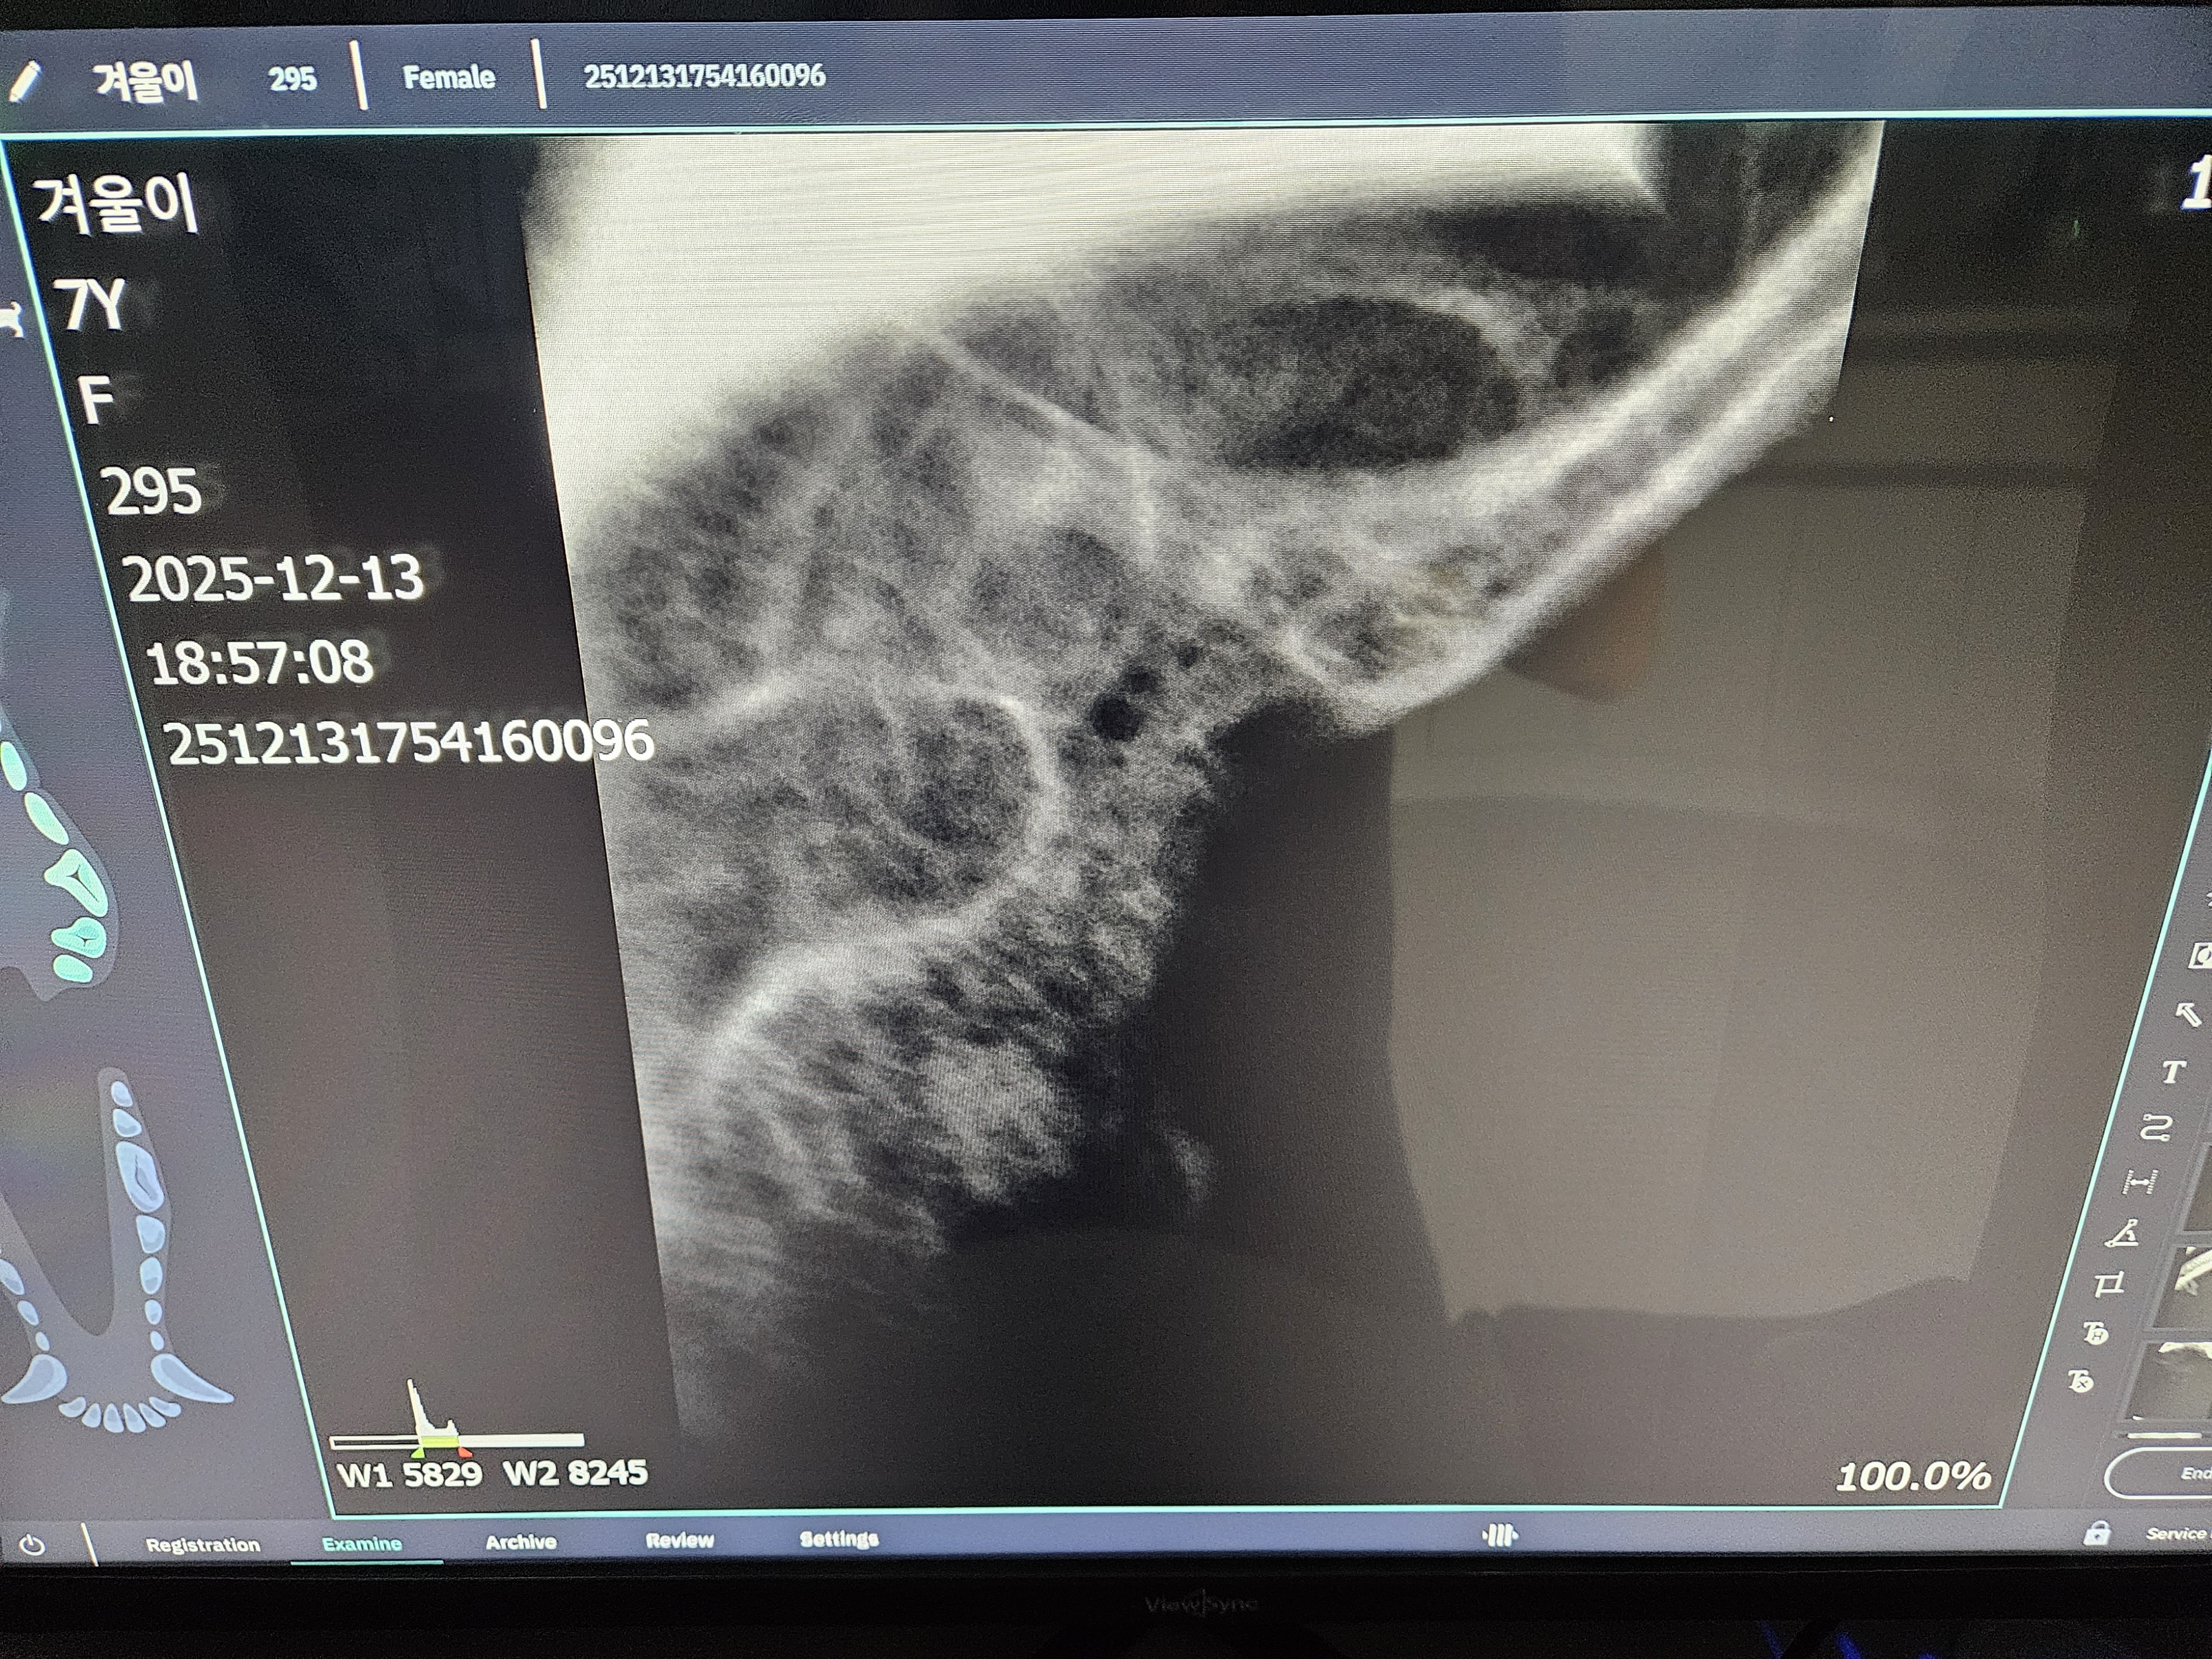

*치아 엑스레이 사진 입니다.

| 치료과정 | 겨울이 염증 수치가 엄청 높았습니다. 보통 정상 수치가 5까지인데 109정도로 엄청 높게 나왔다고 합니다. 염증 수치 같은 경우는 단점이 어떤 부위에 문제가 있는지를 나타내는 수치는 아님. 그런데 겨울이는 구강 안쪽이 엄청 빨개졌었음. 그래서 구내염에 의한 급성염증 수치라고 생각하면 되고, 마취 전에 한 검사는 간수치랑 신장 수치를 체크해주셨는데 콩팥이나 다른 부위는 기능이 정상이라고 하셨습니다. 겨울이 같은 경우는 밥을 잘 못먹었을 뿐이지 간수치나 신장 수치는 특이사항이 없다고 하셨습니다. 겨울이가 입원한 날 빈혈이 너무 심해가지고 수액을 맞았습니다. 그런데 적혈구 개체수도 부족해서 계속 수액을 맞을 수가 없었습니다. 혈액의 적혈구가 부족한혈액이 점점 많아지는 거예요. 항생제 수액으로 마무리 했다고 하셨고,급성 염증 수치는 시간이 지남에 따라서 무조건 좋아진다고 하셨는데, 약은 항생제와 염증 가라앉히는 소염제를 처방해준다고 하셨습니다. 치아 엑스레이 찍은 결과 치조골이라고 해서 이빨에 잡고 있는 뿌리가 어 다 녹아 있었고,그래서 이런 부분들이 이빨의 기능을 상실한 채로 그냥 이가욱씬욱씬한 상태로 있었을거고, 그래서 이빨을 뽑아야 하는 상태라고 하셨습니다. 송곳니는 부러져 있는 부위도 있어서 그런 이빨들은 뿌리 안남기고, 제거를 하셨다고 했습니다. 이빨 자체가 약한 상태이고 전체적으로 발치를 다 한 상태라고 하셨습니다. |